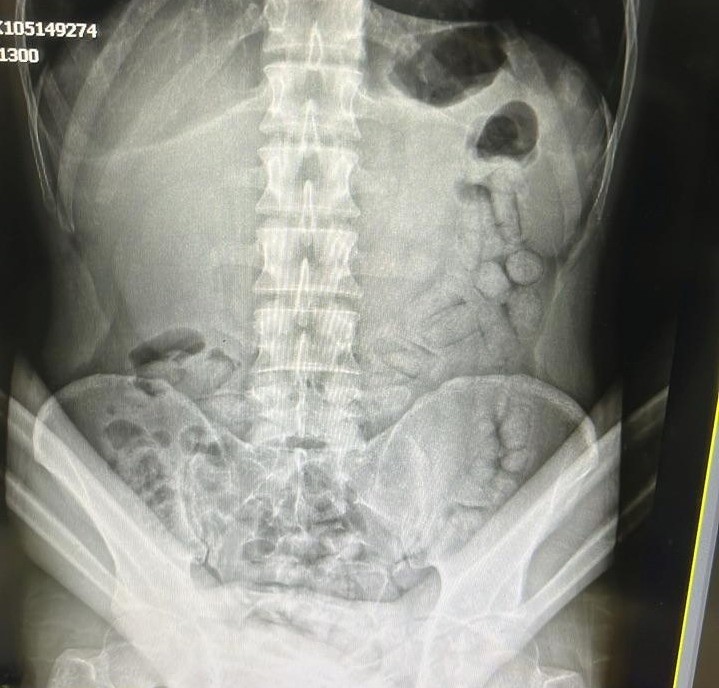

Adli makamların talimatı üzerine Gümüşhane Devlet Hastanesine götürülen şahsa yönelik iç beden muayenesinde bağırsaklarında 55 adet kapsül olduğu tespit edildi. Hastanede yapılan müdahalenin ardından şahsın bağırsaklarından çıkarılan kapsüllerin içerisinde toplamda 317,46 gram metamfetamin ele geçirildi.